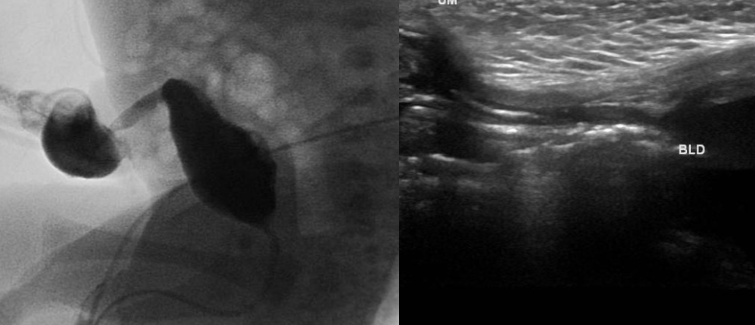

Fistule de l’Ouraque

- Le plus fréquent (50%)

- Fuite d’urine par l’ombilic